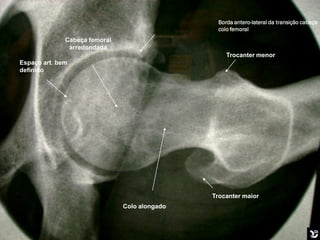

   Esta radiografia mostra bem uma boa mobilização na

incidência de Ducroquet. Podemos visualizar o colo

femoral bem alongado, trocanter menor visível em

perfil internamente.

Borda antero-lateral da transição cabeça

colo femoral

Cabeça femoral

arredondada

Trocanter menor

Espaço art. bem

definido

Trocanter maior

Colo alongado

Esta radiografia mostra bem uma boa mobilização na incidência de Ducroquet. Podemos visualizar o colo femoral bem alongado, trocanter menor visível em perfil internamente. Boa mobilização

Borda antero-lateral datransição cabeça colo femoral Cabeça femoral arredondada Trocanter menor Espaço art. bem definido Trocanter maior Colo alongado Boa mobilização